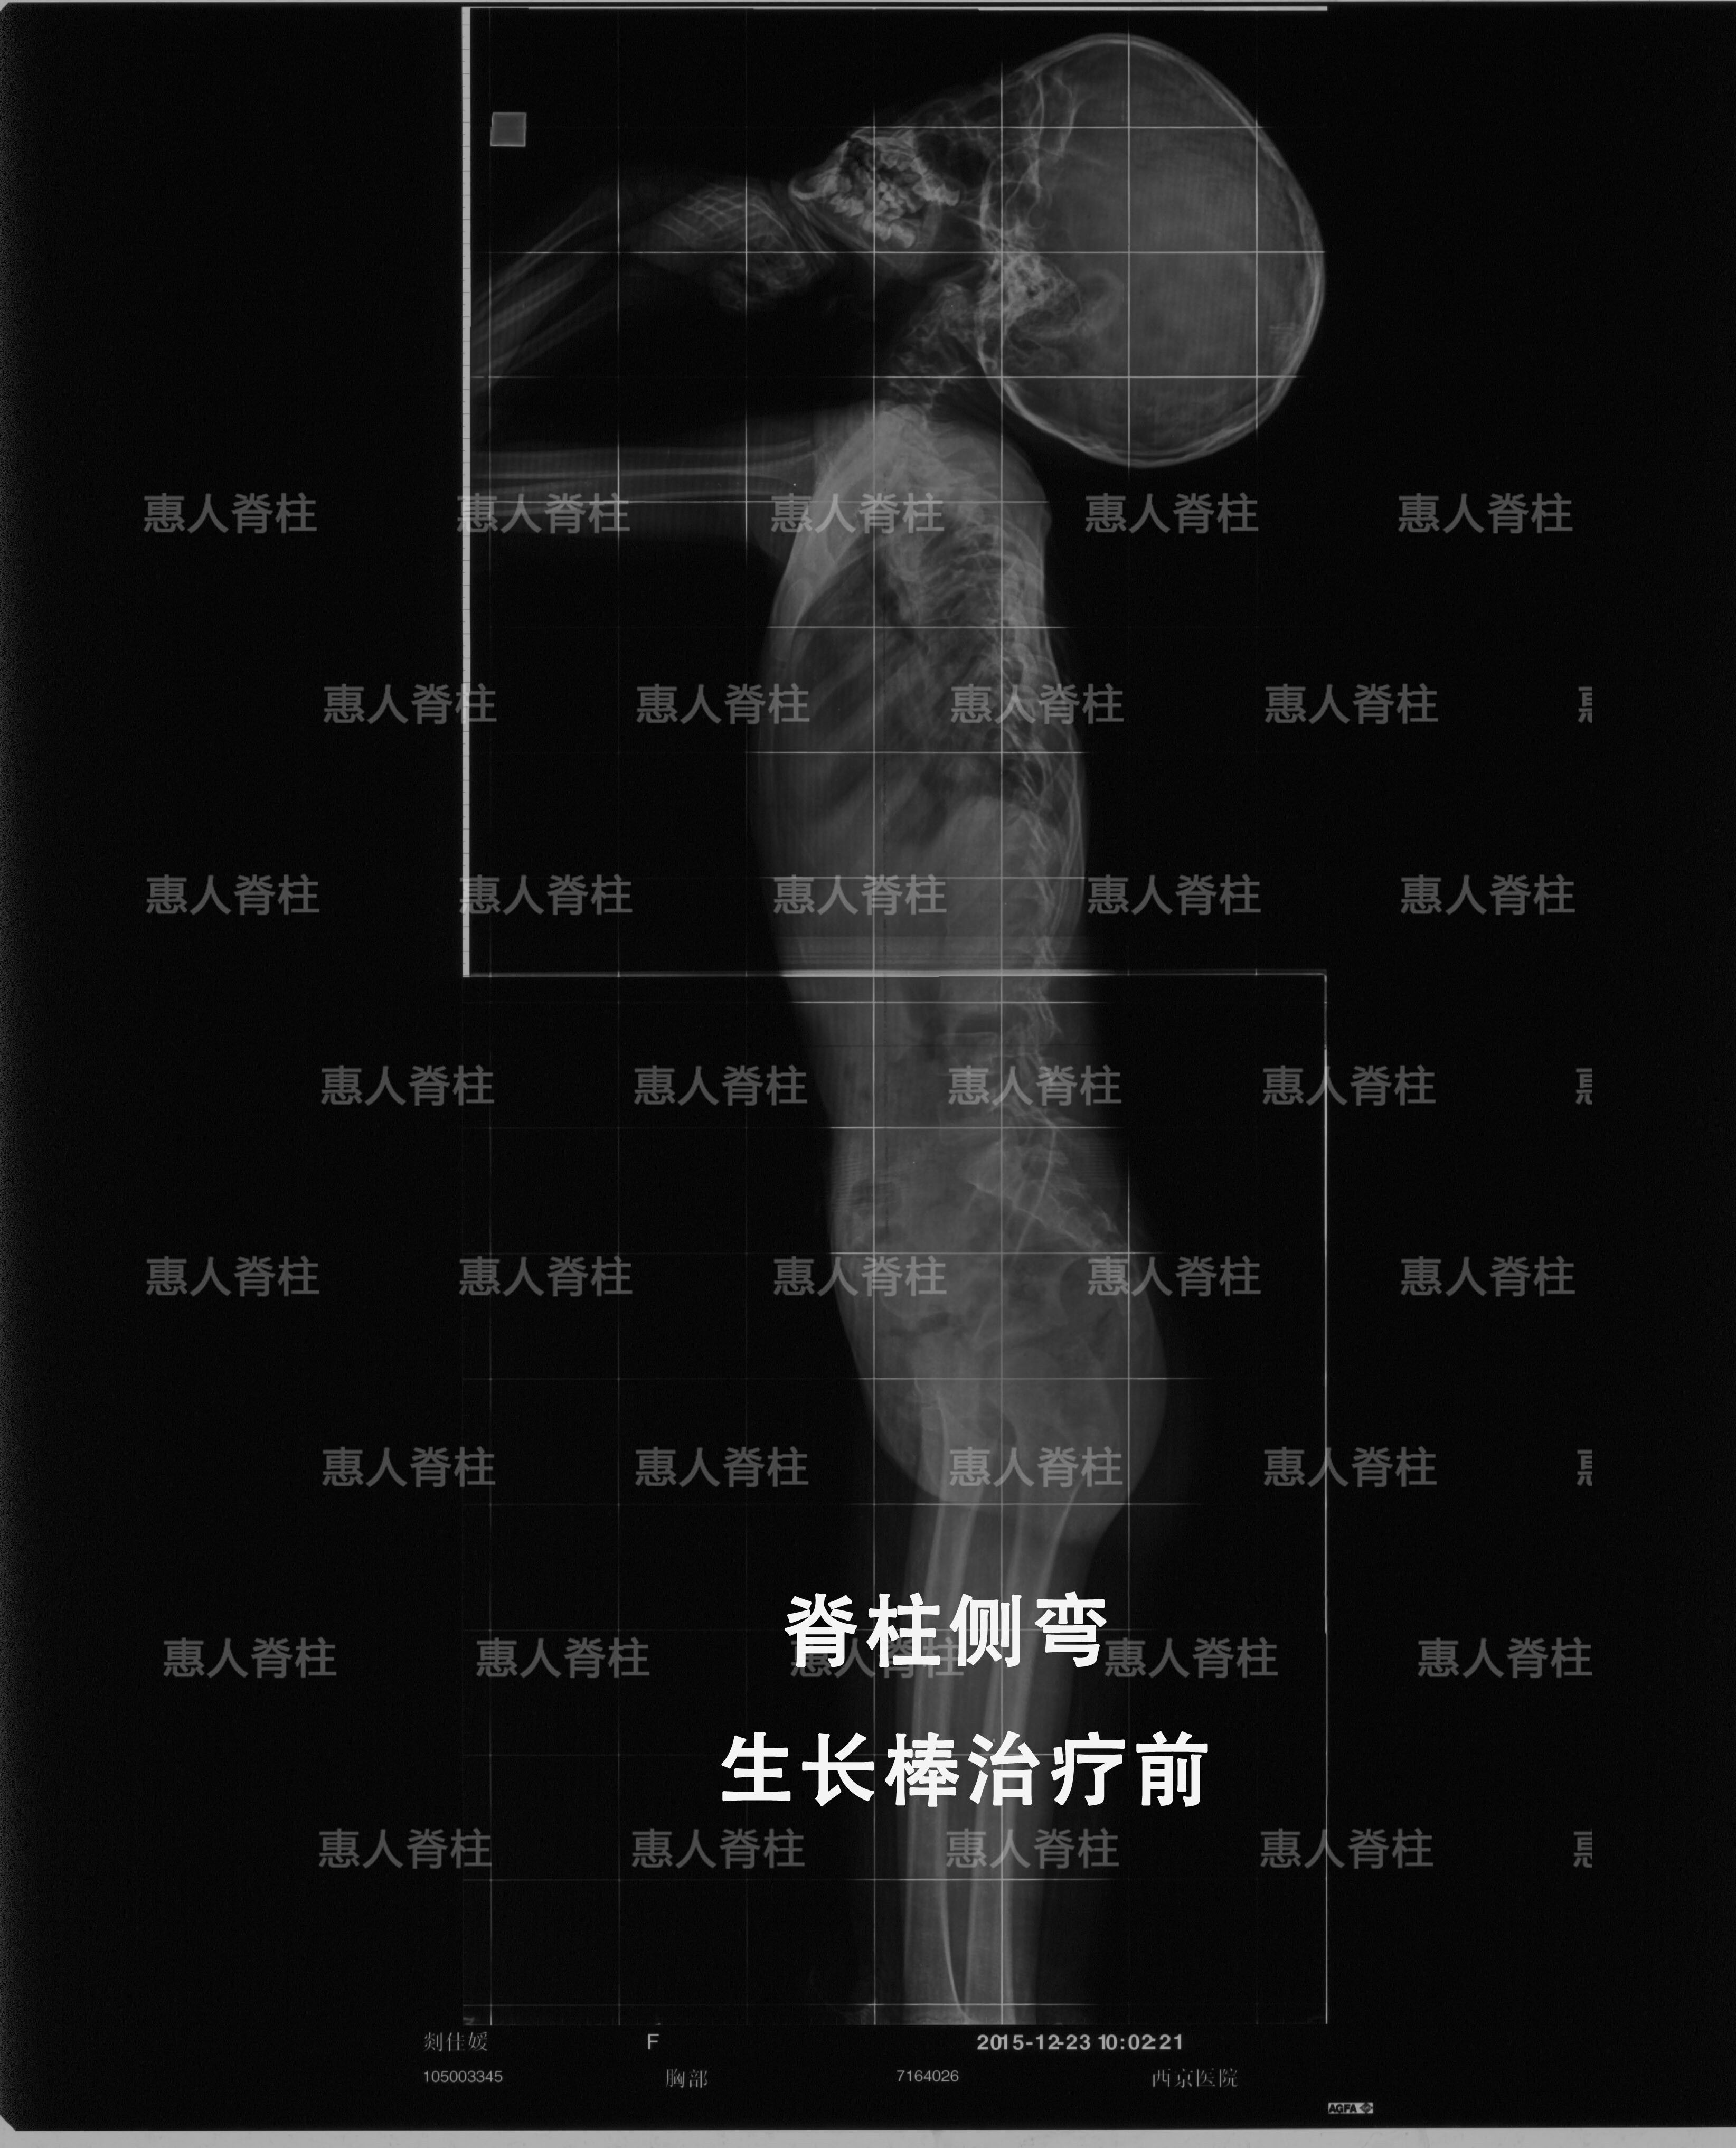

由于六月为儿童脊柱侧弯进行的免费治疗活动,近期接诊很多年龄非常小的脊柱侧弯患儿,对于这种早发性脊柱侧弯,我们会有一种针对性的治疗方式——生长棒治疗。

早发性脊柱侧凸(EOS)泛指发生于5岁以前低龄儿童且有较大进展风险的脊柱侧凸,其病因学包括婴幼儿特发性、先天性、神经肌源性及综合征相关等。

随患儿的身高发育呈进行性加重,可导致严重的畸形,影响心肺发育,压迫脊髓,严重者可导致神经功能受损,甚至因心肺功能衰竭而死亡。

EOS患儿的脊柱畸形往往发生于脊柱纵向生长的高峰期,畸形常随着脊柱的快速增长而进行性加重。

首先是矫形支具矫正的保守方法,试图矫正部分畸形或控制畸形的发展速度,待年龄大了以后在进行矫正固定融合手术;但是往往由于幼儿年龄较小而无法配合切实佩带支具,或者是畸形发展速度较快而支具无法控制,生长棒既矫正畸形又不影响儿童的生长发育,适用于年龄小、骨骼发育潜力大的患儿。